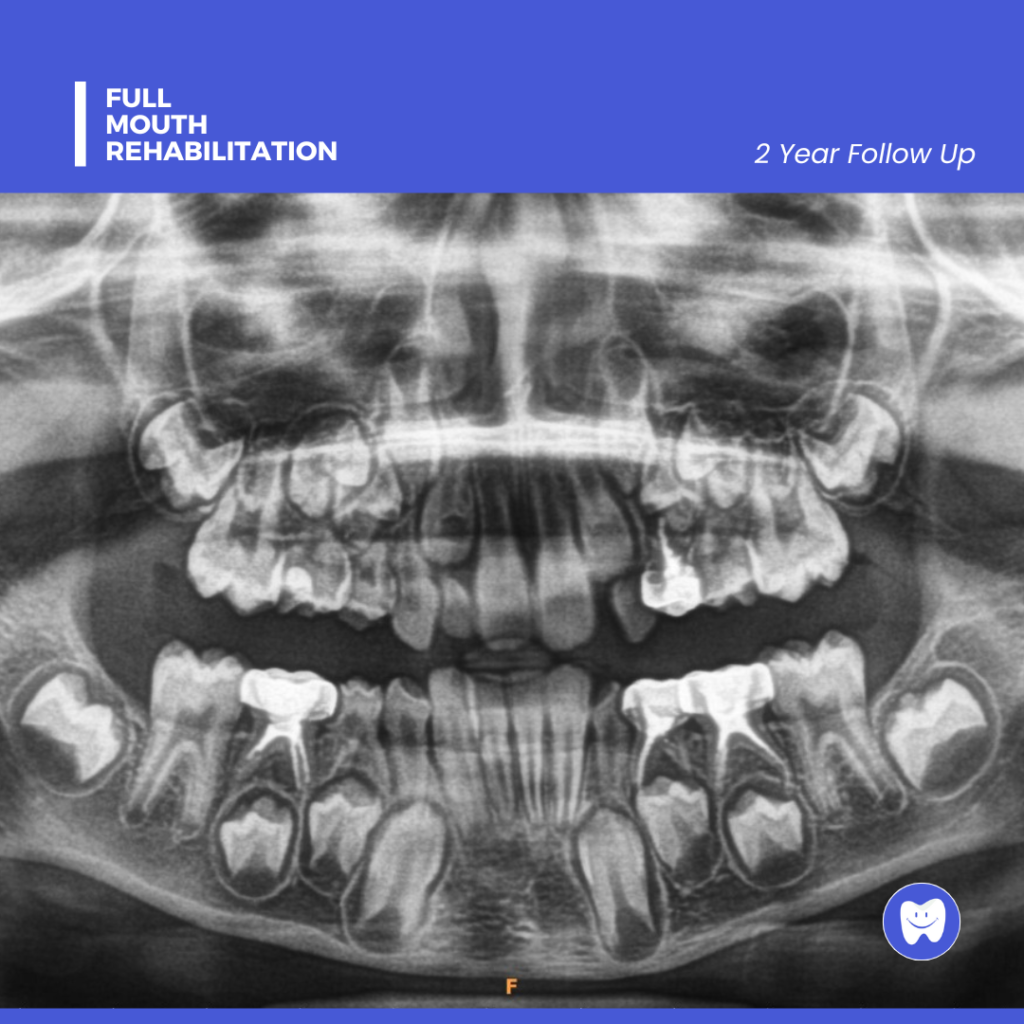

A thorough examination and diagnostic tests (such as digital X-rays) to assess the condition of all teeth and gums.

Post-Treatment Care

Aftercare instructions are given, and follow-up visits are scheduled to monitor progress and ensure the best outcome.

Improved Oral Health

Addressing multiple dental issues at once leads to better overall health and function.